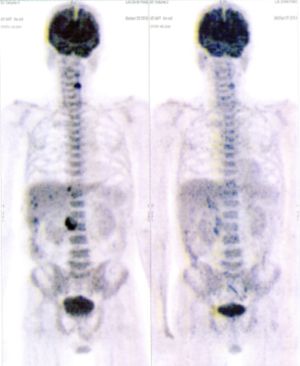

CASE NO: 7 (BREAST CANCER)

A middle-aged woman treated for breast cancer now presents with bone and liver metastases. After a few treatment, most of the cancer went into remission, and the remaining ones are less active.

CASE NO: 8 (BREAST CANCER)

A middle-aged women treated for breast cancer now present with bone and right lung metastases. After just 2 treatment, almost all the cancer went into remission, but treatment is continuing to prevent recurrence.

CASE NO: 9 (NHL + LUNG CANCER)

A middle-aged man successfully treated for non-Hodgkin’s lymphoma, came back with massive right lung and pleural cancer. After just 2 treatment, all the cancer went into remission. Treatment is continuing to prevent recurrence.